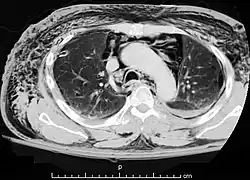

Die Computertomographie des Brustkorbs zeigt Luft in der Unterhaut, im Mediastinum und in der Rückenmuskulatur.

Die Diagnose eines Pneumomediastinums wird mittels Bildgebung, entweder mittels konventioneller Röntgenaufnahme (Röntgen-Thorax) oder mittels Computertomographie des Brustkorbs, gestellt. Die Computertomographie ist sensitiver als das konventionelle Röntgen. Neben dem Nachweis auch kleinster Luftansammlungen im Mediastinum liefert die Computertomographie auch Hinweise auf die mögliche Ursachen (Ätiologie).